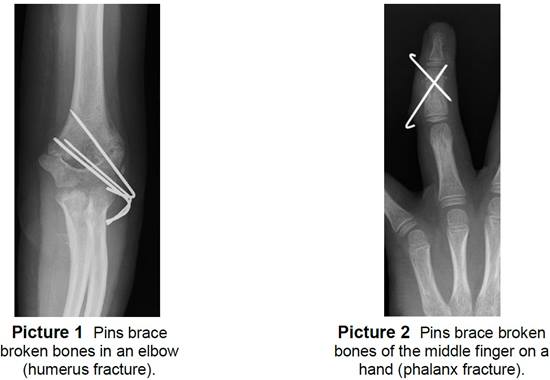

Percutaneous in medicine means that something is pushed through the skin instead of cutting the skin open like in other surgeries. With percutaneous pinning, an orthopedic surgeon (bone doctor) pushes a metal pin or wire through the skin and into the bone. One end of the pin sticks out of the skin while the other stays in the bone (Pictures 1 and 2).

- This technique holds a broken bone (fracture) together and keeps it still until it heals.

- The number of pins needed depends on how bad the fracture is and where it is located.